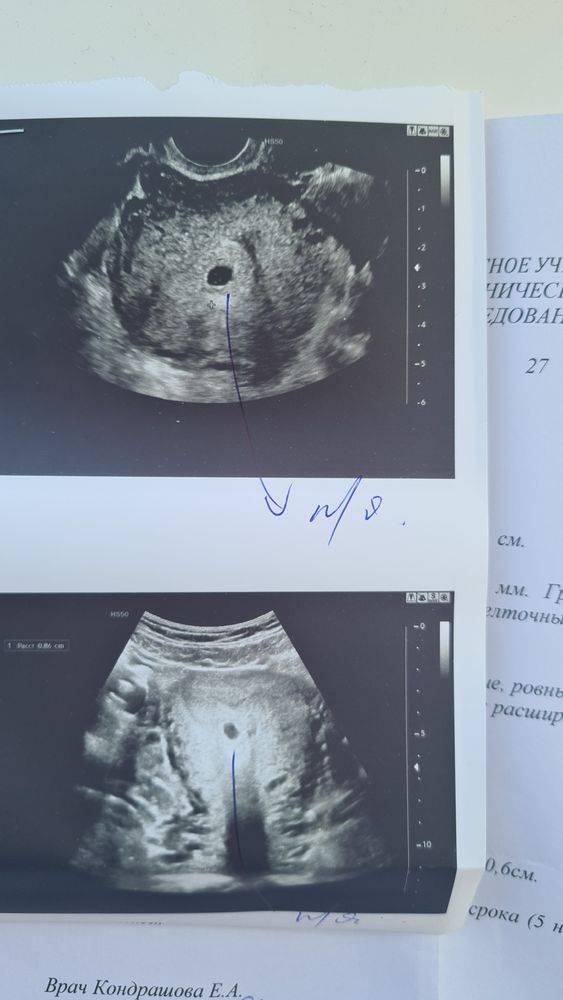

⚠️Узи в 5 недель и 2 дня ⚠️

На узи плодное яйцо 7 мм, желточный мешочек 2 мм, узист сказала маловато для моего срока, у меня выделения темно бежевые мажущие (завтра на приём в жк), посмотрела по таблицам вроде плодное яйцо соответствует сроку. Я переживаю из за предидущей замершей...скажите пожалуйста кто нибудь делал узи на таком сроке, какой у вас был размер плодного яйца? На узи гематомы нет. Отслойки нет...почему мажет то...😭